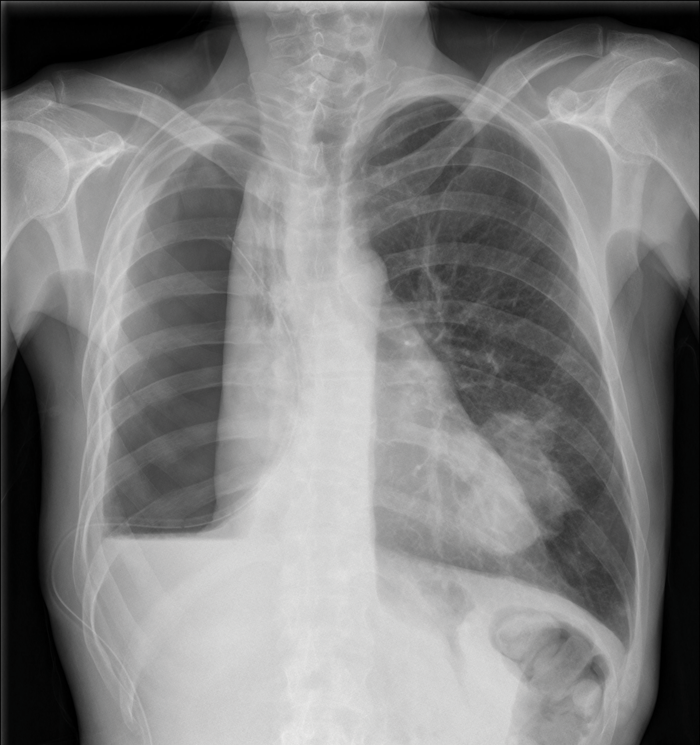

A chest X-ray is usually the first-line investigation; 94% of patients with MPM have a unilateral pleural effusion, although the chest X-ray may be normal or show another asbestos-related lung disease, see table 3.

Where there is a suspicion of MPM, the BTS recommends investigation with a contrast enhanced CT scan with intravenous contrast timed to enhance the pleura.2 Figure 1, shows malignant mesothelioma, with concentric pleural thickening extending over the mediastinal surface.